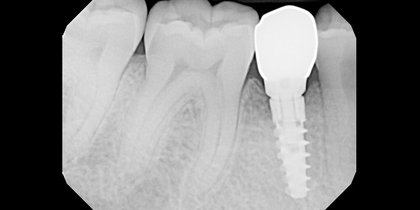

• Tooth #14 is replaced using a Glidewell HT Implant. thumbnail image

Single-Unit Posterior

Tooth #14 is replaced using a Glidewell HT Implant.